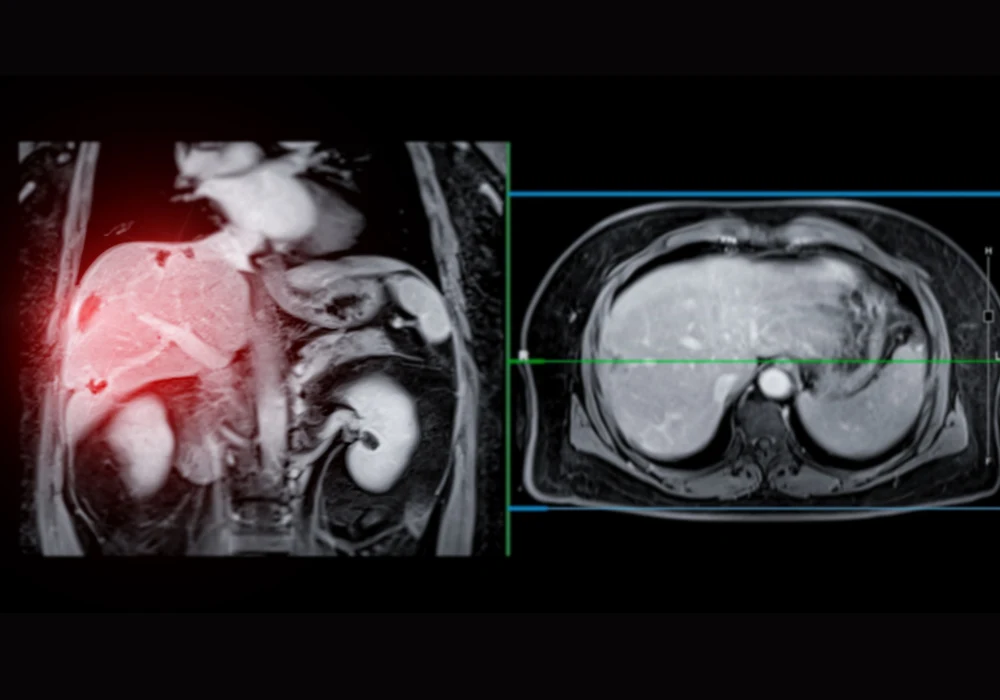

Magnetic resonance imaging (MRI) is a cornerstone of liver lesion detection, particularly when enhanced with gadoxetate disodium during the hepatobiliary phase. While high-field MRI systems at 1.5 T or 3 T have well-established flip angle (FA) protocols to maximise image quality, the rise of mid-field systems at 0.55 T—offering cost-efficiency, comfort and fewer artefacts—calls for tailored imaging parameters. In this context, determining the optimal FA for hepatobiliary imaging at 0.55 T is crucial, especially in patients with metastatic neuroendocrine tumours.

To identify the most effective FA for liver imaging at 0.55 T, researchers initiated a study combining theoretical modelling with a prospective clinical trial. Initial signal intensity calculations, based on established MRI physics, predicted peak liver enhancement in the 23–28° range. These estimates laid the groundwork for clinical validation using actual patient data. From February to December 2023, fourteen patients with known or suspected metastatic neuroendocrine tumours underwent hepatobiliary-phase liver MRI using a low-field scanner. The protocol incorporated a series of T1-weighted VIBE sequences enhanced with deep learning denoising and Dixon water-fat separation, with FAs ranging from 10° to 70°.

The study revealed that a FA of 30° consistently delivered superior liver-lesion and liver-vessel contrast. Specifically, liver-lesion contrast peaked at 97.7% at 30°, showing a marked improvement over both lower FAs (10–20°) and higher ones (40–70°). Similarly, liver-vessel contrast was highest at 30° (96.0%), surpassing other values, particularly those below 20° or above 60°. However, the highest liver signal intensity was recorded at a FA of 20°, where the value reached nearly 100%, suggesting that this angle may be preferable when pure liver signal clarity is the priority.

Importantly, while these findings align with prior research conducted at higher field strengths—which reported optimal FAs between 25° and 40° for image quality and lesion detection—the current study refines this understanding for the unique dynamics of 0.55 T systems. Notably, increased flip angles beyond 40° yielded diminishing returns, particularly for liver-lesion visibility, highlighting the non-linear relationship between FA and image contrast at lower field strengths.